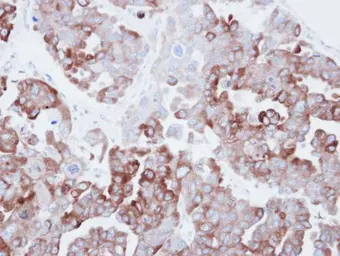

Anti-Fatty Acid Synthase antibody [N1], N-term used in IHC (Paraffin sections) (IHC-P). GTX109833

GTX109833 IHC-P Image

Immunohistochemical analysis of paraffin-embedded human ovarian carainoma, using Fatty Acid Synthase(GTX109833) antibody at 1:500 dilution.

Antigen Retrieval: Trilogy™ (EDTA based, pH 8.0) buffer, 15min